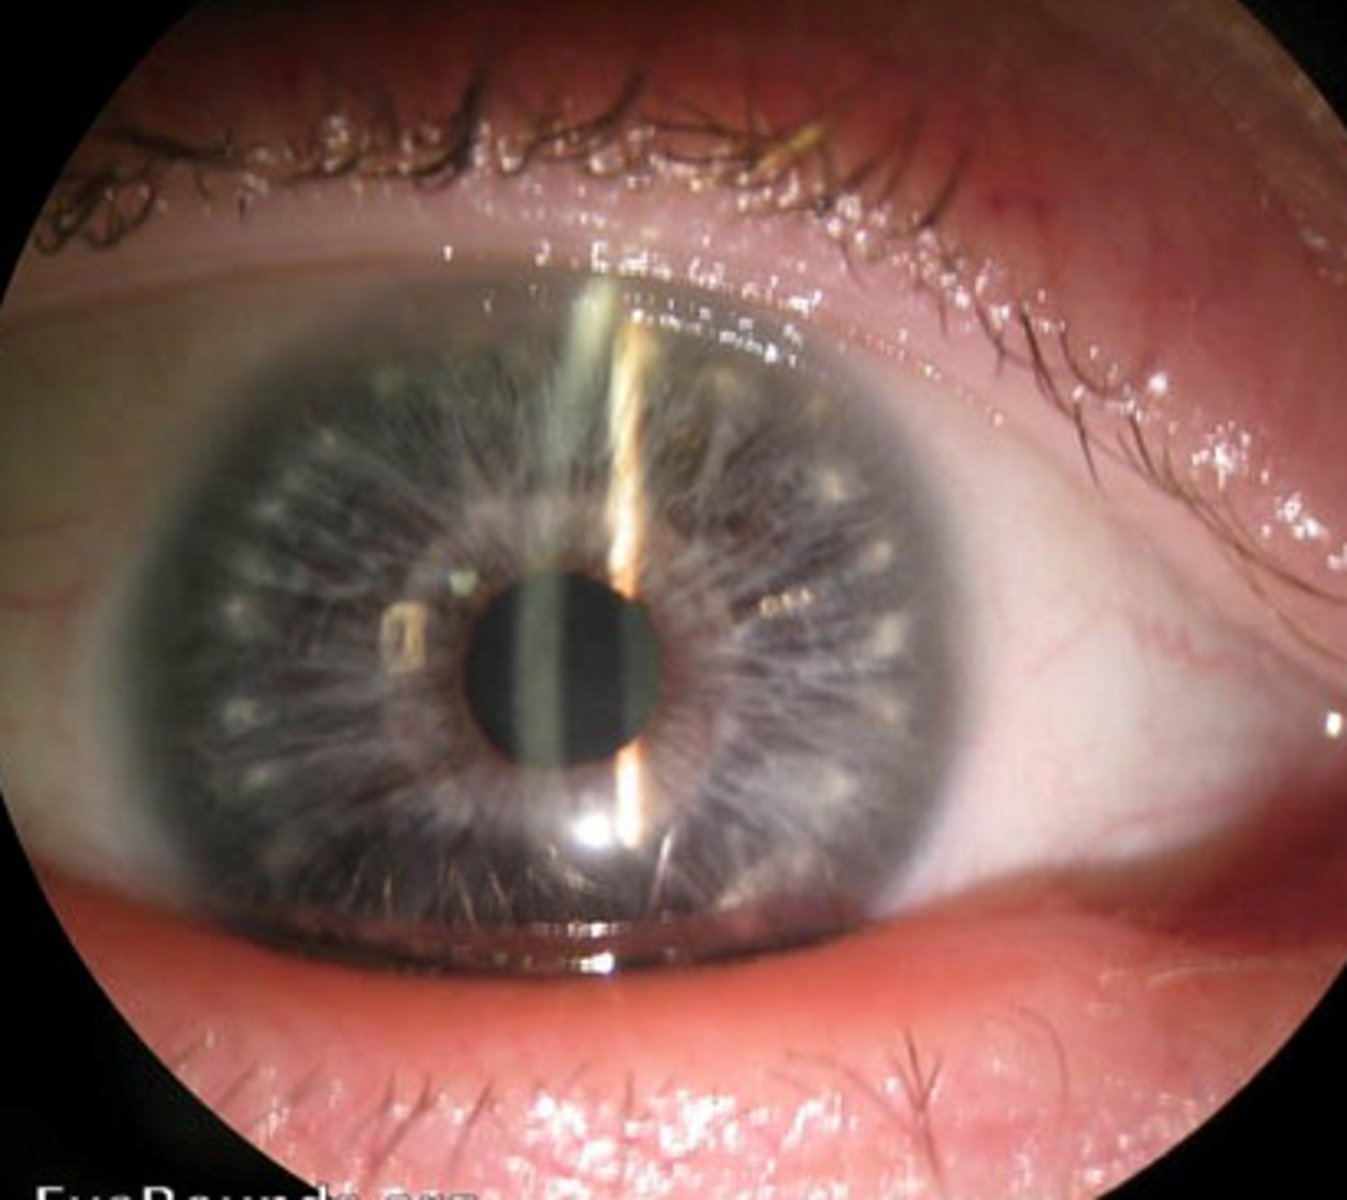

a patient has the following features. what do you suspect?

brushfield Spots

down Syndrome